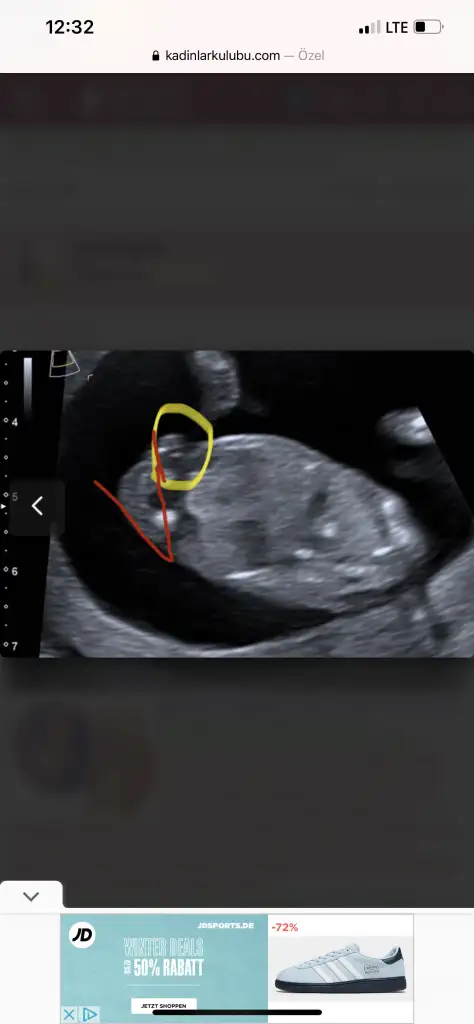

Evet belli olur o haftadaKizlar perşembe ben 14 haftalık olucam Allah izin verirse şehir hastanesi rica etsem cinsiyet söyler mi artık belli olur herhalde??

Ben olurda kıza döndü derse söylemeyeceğim kimseye 7 8 ayda birden görsünlerAy ciddi manada dejavu bukızsa net demez bence yüzdelikli konuşur çünkü sonradan çıkabiliyormuş benim doktor hiç söylemedi de bacak arası boştu yani. net konuşmazsa kimseye bişey deme netleşene kadar hatta ben senin yerinde olsam erkek dese bile kız olabilirmiş derim uzunca zaman millet benle uğraşıyor birazda ben onlarla uğraşayım hesabı